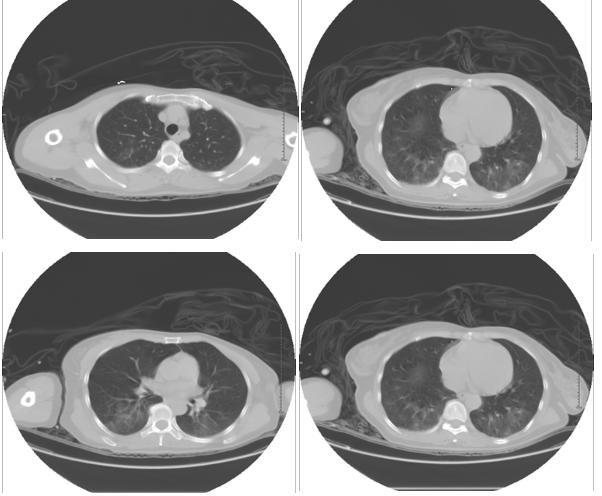

可是上帝真的不公平,也许是因为太绝望,也许是经历太多痛苦,所以你要选择离开人世。下面讲的这个故事是一位轻生的患者服用大量百草枯的案例,很痛心,因为最后她还是走了。凌晨的夜晚,那个拥有片刻宁静的重症监护室被急诊抢救室送上来的一位患者打破了。急诊科医护人员,急忙的将一位表情痛苦的患者用平车直接转运到了我们科。患者不时*吟呻**着,*班交**医生喘着大气说,患者56岁,女性,自服百草枯3小时入院,已经洗胃,患者心率快,呼吸急促,很快会出现呼吸衰竭,肺水肿,需要在重症监护室进行抢救,需要立即行血液灌流治疗,也很有可能要机械通气。下面是急诊查的胸部CT,当时已经有炎症渗出的表现。

然后急查的血气分析提示低氧血症,氧和指数仅有两百多。血常规提示,白细胞三万多,中性粒细胞高,肾功能轻度损害,低钾血症,肝功能无明显异常,但全身炎症反应明显,有高热,气喘等表现。